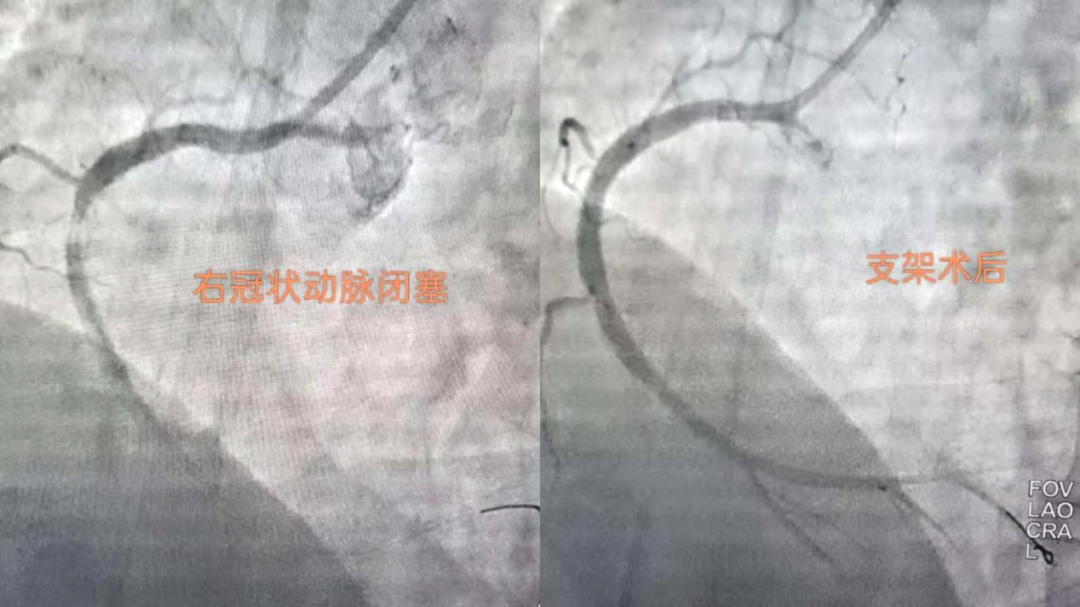

搶時間就是搶生命!06:46穿刺,06:47成功,06:49冠脈造影明確:右冠狀動脈中段完全閉塞。導絲迅速通過,支架精準植入,07:03血流恢復,手術成功結束?;颊咝赝疵黠@緩解,生命體征趨于平穩(wěn)。從入院到血管再通,不到兩小時。